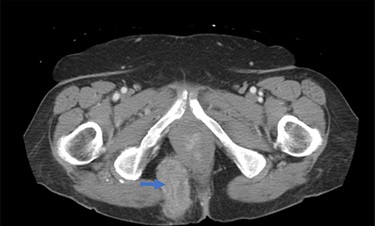

Once the hernia was completely reduced, the hernia sac was resected. The muscular defect of the pelvic floor was delineated. The pelvic floor was reconstructed, and the muscular defect was reapproximated from lateral to medial using 3-0 V-Loc running sutures in a tension-free manner. An 8 × 8 cm synthetic bioabsorbable Phasix mesh was used to reinforce the repair (Fig. 3). To prevent the rectum from falling back into the pelvis, a suture rectopexy was performed in the traditional fashion by clearing the sacral promontory from overlying soft tissue, exposing the periosteum of the sacral promontory and using silk sutures to attach the rectum to the sacrum. The pelvis was reperitonealized using running 3-0 V Loc absorbable sutures. Post-operatively, the patient had return of bowel function, adequate pain control, tolerated a soft diet and was discharged after 2 days. The patient had significant improvement in her fecal incontinence at her 4-week follow up visit, and post-operative CT demonstrated resolution of the hernia (Fig. 4).

Post-operative CT demonstrating mild fluid in pelvis and resolution of the hernia (black arrow).